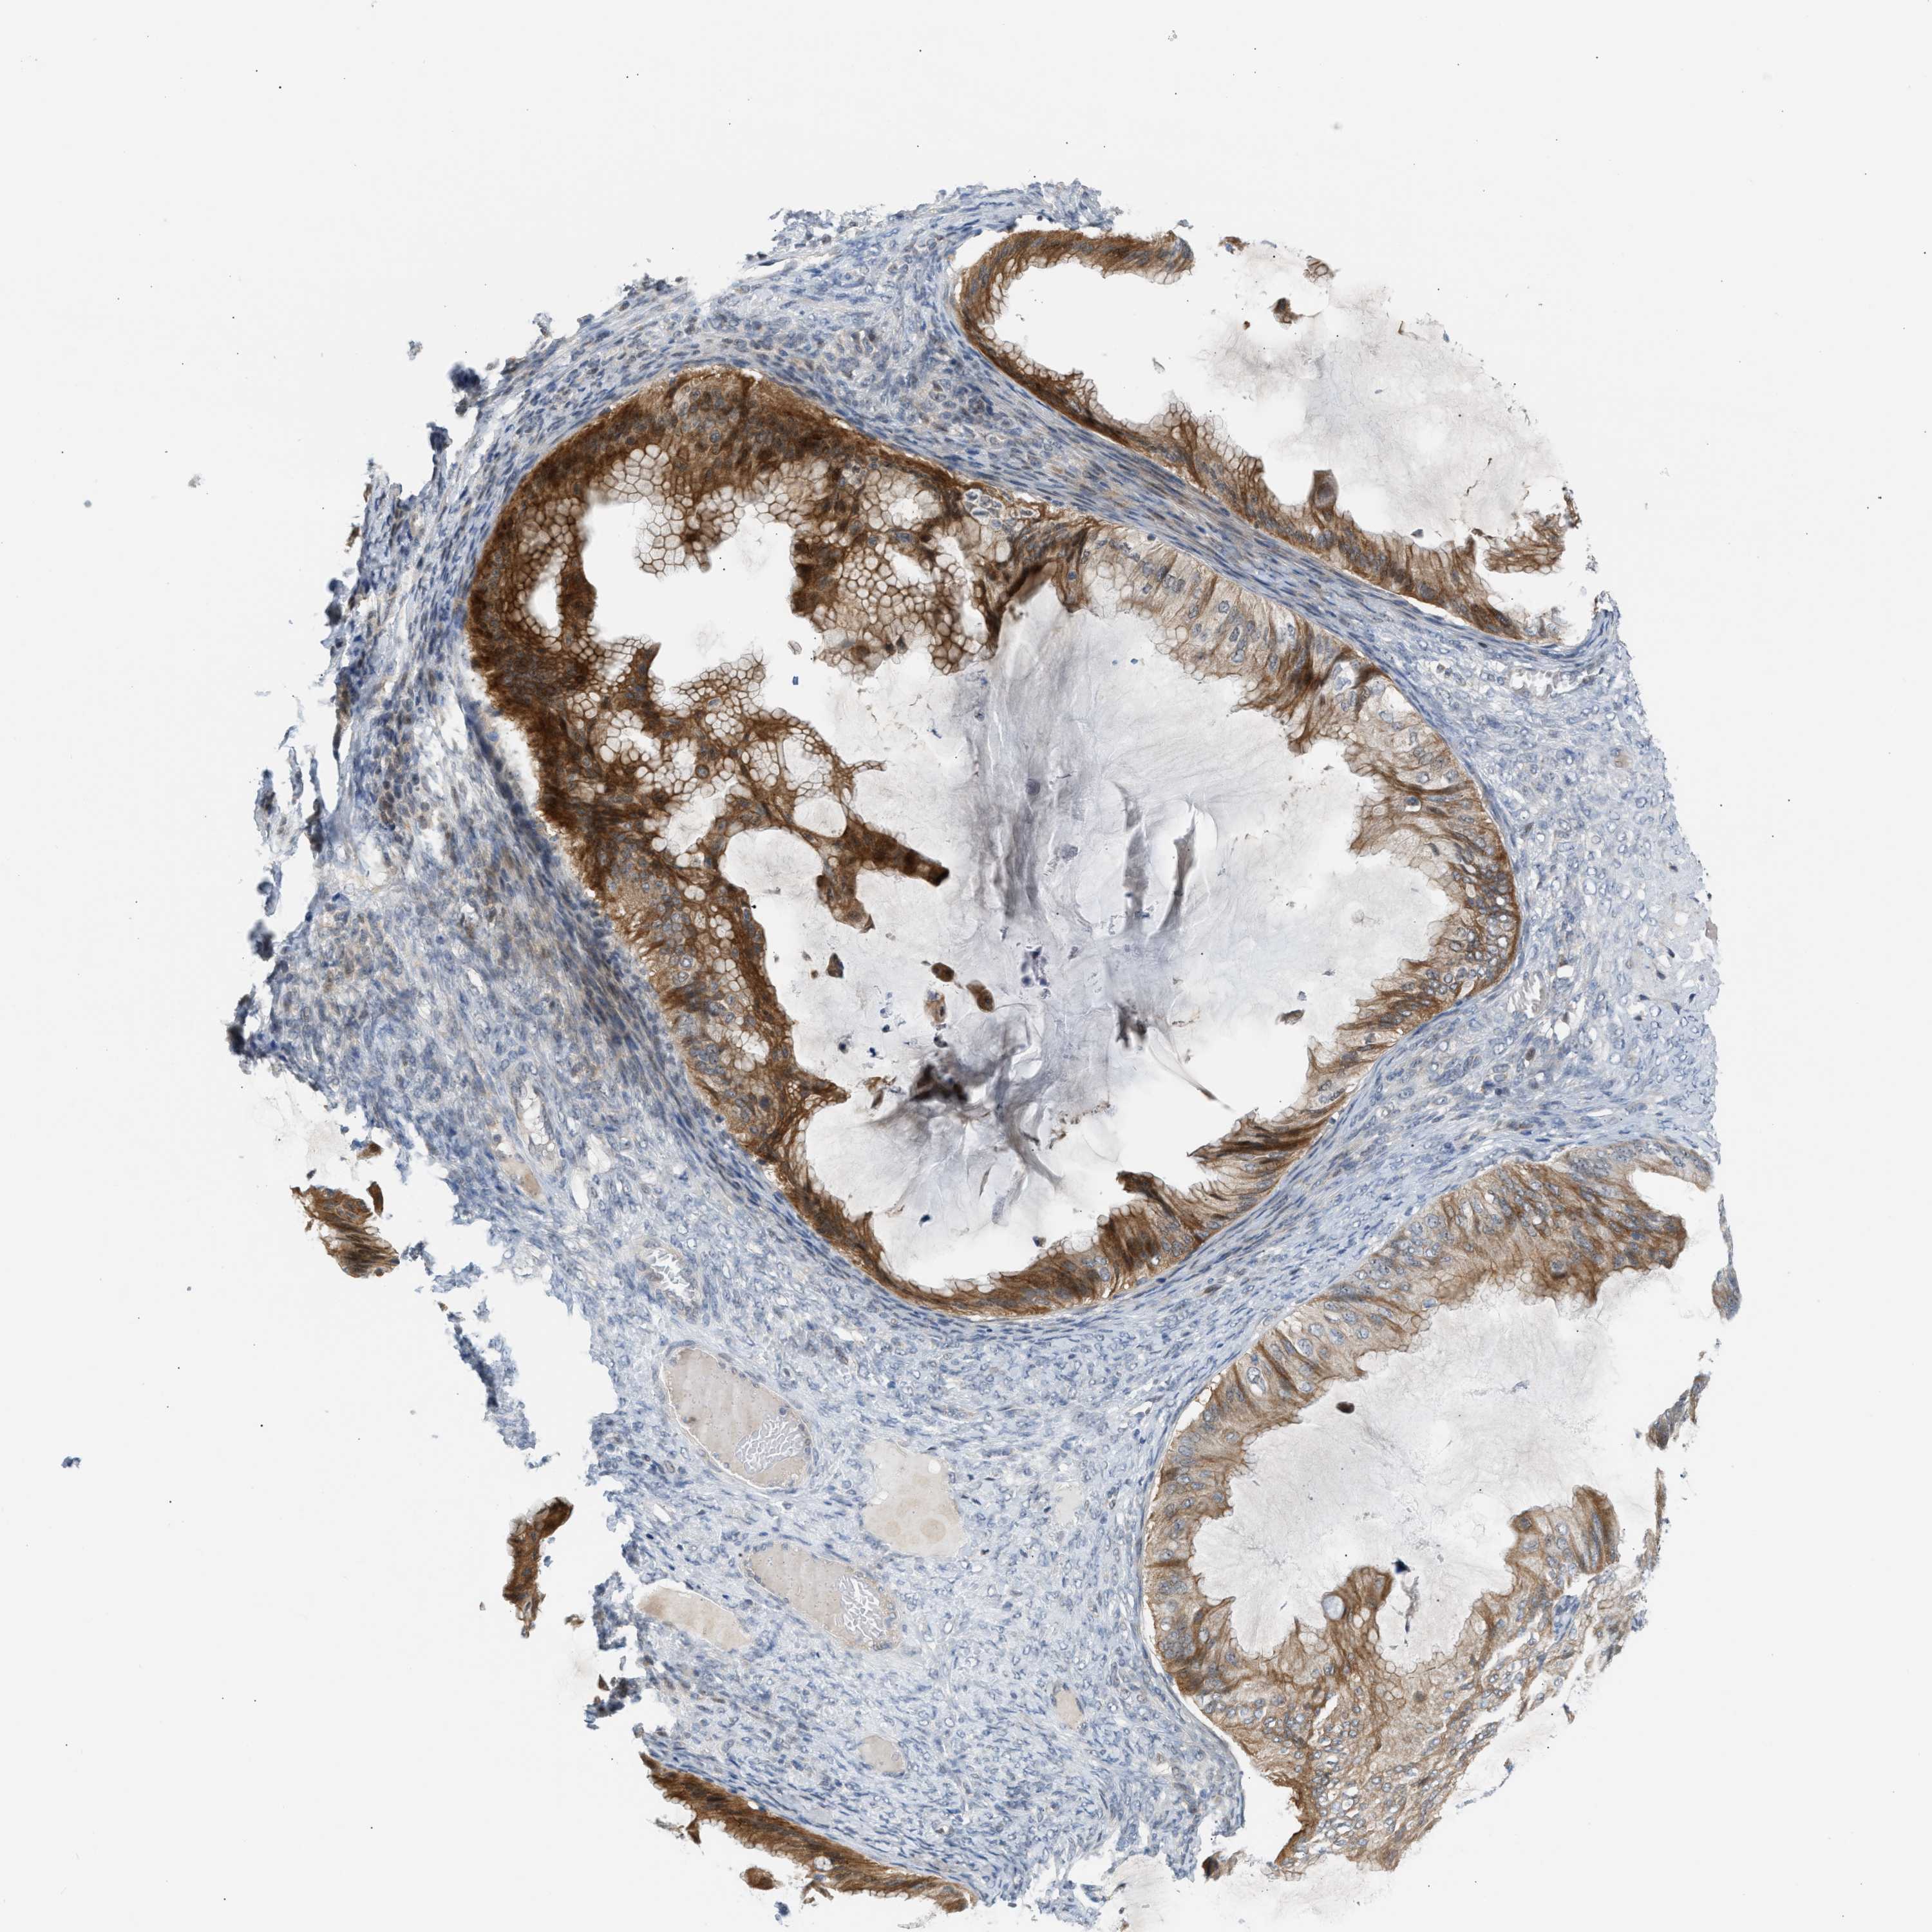

OVARIAN CANCER - Protein expressioni

A mouse-over function shows sample information and annotation data. Click on an image to view it in a full screen mode. Samples can be filtered based on level of antibody staining by selecting one or several of the following categories: high, medium, low and not detected. The assay and annotation is described here.

Note that samples used for immunohistochemistry by the Human Protein Atlas do not correspond to samples in the TCGA dataset.

Antibody stainingi

Antibody staining in the annotated cell types in the current human tissue is reported as not detected, low, medium, or high, based on conventional immunohistochemistry profiling in selected tissues. This score is based on the combination of the staining intensity and fraction of stained cells.

Each image is clickable and will lead to virtual microscopy that enables deeper exploration of all samples and also displays staining intensity scores, fraction scores and subcellular localization as well as patient and tissue information for each sample.

Antibody CAB020139

Staining

High

Medium

Low

Not detected

Intensity

Strong

Moderate

Weak

Negative

Quantity

>75%

75%-25%

<25%

None

Location

Nuclear

Cytoplasmic/membranous

Cytoplasmic/membranous,nuclear

Cystadenocarcinoma, serous, NOS

Carcinoma, endometroid

Cystadenocarcinoma, mucinous, NOS

Carcinoma, NOS